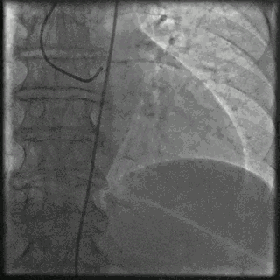

冠動脈造影は冠動脈疾患の診断のゴールドスタンダードで、確かに正確ですが、侵襲的で、カテーテル検査室に入院する必要があり、主動脈の狭窄が75%以上であれば、ステントの留置を考慮しなければならないという欠点があります。冠動脈CTは非侵襲的な検査で、入院の必要はなく、外来で行うことができるが、精度が低く、繰り返し撮影して問題を明らかにする必要がある。

重症の冠動脈疾患では、ステント留置術や冠動脈バイパス手術が必要になることが多い。冠動脈疾患を治す治療法だと思っている人がいるが、そうではない。これらの治療は、血流を再確立する方法であり、冠動脈疾患の患者にもう一度やり直すチャンスを与える方法に過ぎない。ステントを埋め込んだにせよ、バイパスを作ったにせよ、これらのステントや橋渡しとなる血管は、できるだけ開いた状態を保つために、長期間の投薬と健康的な生活習慣の維持が必要です。うまく維持できれば10年、20年と長持ちし、うまく維持できなければ3年、2年、5年とすぐにまた詰まってしまう。

冠動脈疾患患者はプラークを安定させ血栓症を予防するためにアスピリンとスタチンを長期間服用し、高血圧、糖尿病、高脂血症などの基礎疾患を有する患者は基礎疾患の治療に注意を払い、血圧、血糖、血中脂質を標準までコントロールすることを提案する。冠動脈狭窄が75%以上の患者、あるいは狭心症発作や急性心筋梗塞が頻発する患者には、ステント治療が可能である。冠動脈に複雑な病変があったり、より多くの基礎疾患がある患者には、医師の指導の下、外科的バイパス移植術などのさらなる治療を行うことができる。

冠動脈疾患(CHD)とは、冠動脈が様々な原因により狭窄・閉塞し、その結果、虚血、低酸素、心筋細胞の壊死を引き起こす症候群である。診断されたら、積極的に生活習慣を改善し、定期的に薬を服用することが必要であり、必要に応じてステント治療や冠動脈バイパス術を行うことが可能である。

冠動脈性心疾患と診断されたら、日常生活ではアスピリンやスタチンの長期使用に注意を払い、狭心症発作のある患者にはニトログリセリンを常備すべきである。狭心症発作の頻度が高く、冠動脈の狭窄が75%以上、あるいは急性心筋梗塞のある患者には、ステント治療が考慮される。複雑な病態の患者に対しては、必要であればバイパス治療も可能である。治療を標準化する一方で、病態の変化を観察し、定期的に見直すことにも注意を払う必要がある。

さらに、薬物療法が無効な重度の狭窄患者や急性心筋梗塞患者には、心臓ステント植え込み術が必要となる場合もある。重度の3枝病変や左主幹病変では外科的心臓バイパス移植術が必要になることもある。